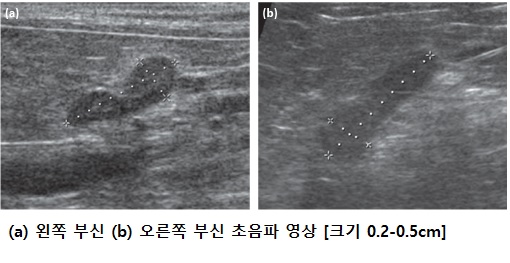

부신이라고 하는 장기는 좌우 콩팥 근처에 있는 아주 작은 장기다. 크기는 1cm도 되지 않아 정상적인 경우 엑스레이로는 보이지 않고 초음파로 숙련된 수의사가 주의 깊게 관찰해야만 확인할 수 있다. 크기는 작지만 다양한 호르몬을 합성하고 분비하는 기능을 가지고 있다.

기본적인 혈액검사에서 ALP 상승 같은 호르몬질환을 의심할 수 있는 수치변화가 있다면 쿠싱병에 대한 추가적인 검사로 복부초음파를 통한 간 평가와 부신 크기 평가가 필요하고, 호르몬인 코티솔 농도검사가 필요하다.